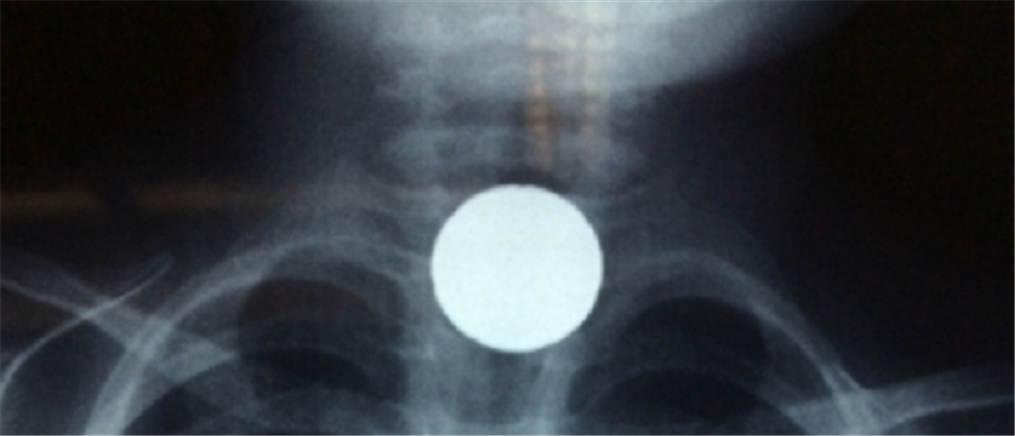

Κρήτη: Παιδί κατάπιε κέρμα και του στάθηκε στον λαιμό (εικόνες)

Περιπέτεια για το 4χρονο και λαχτάρα για τους δικούς του ανθρώπους, λίγο πριν το γύρισμα του χρόνου. "Συναγερμός" σήμανε στο ΠΑΓΝΗ.